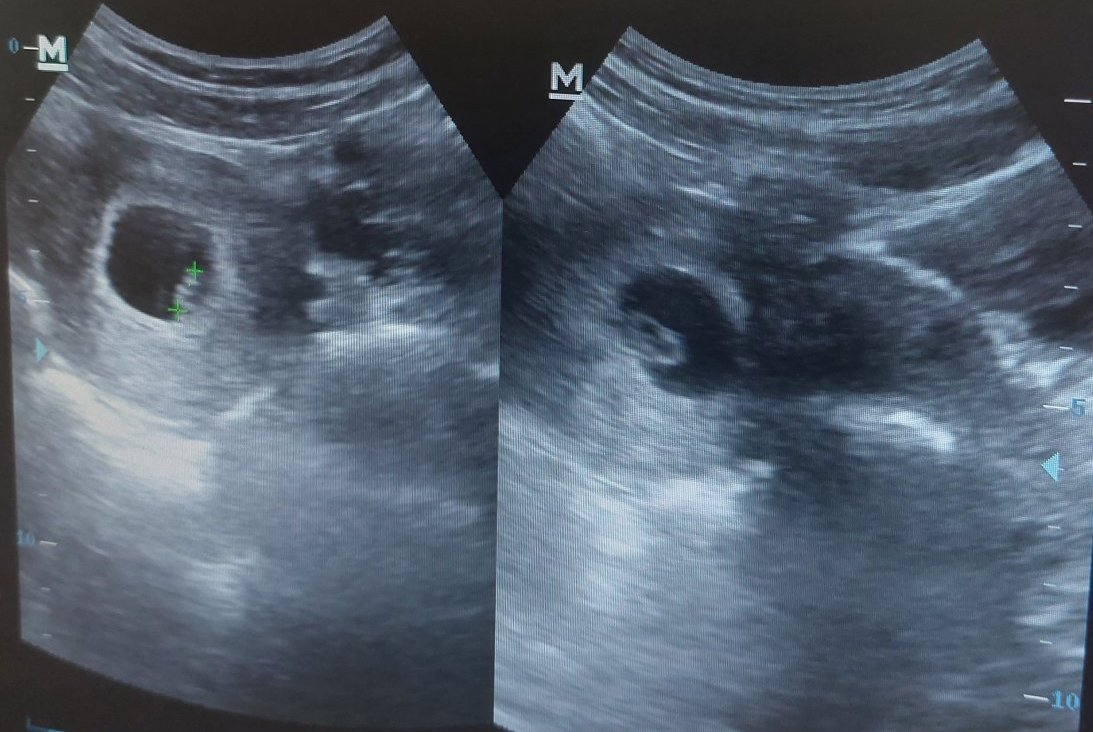

Какви са резултатите от изследванията и прегледите в ранна бременност?